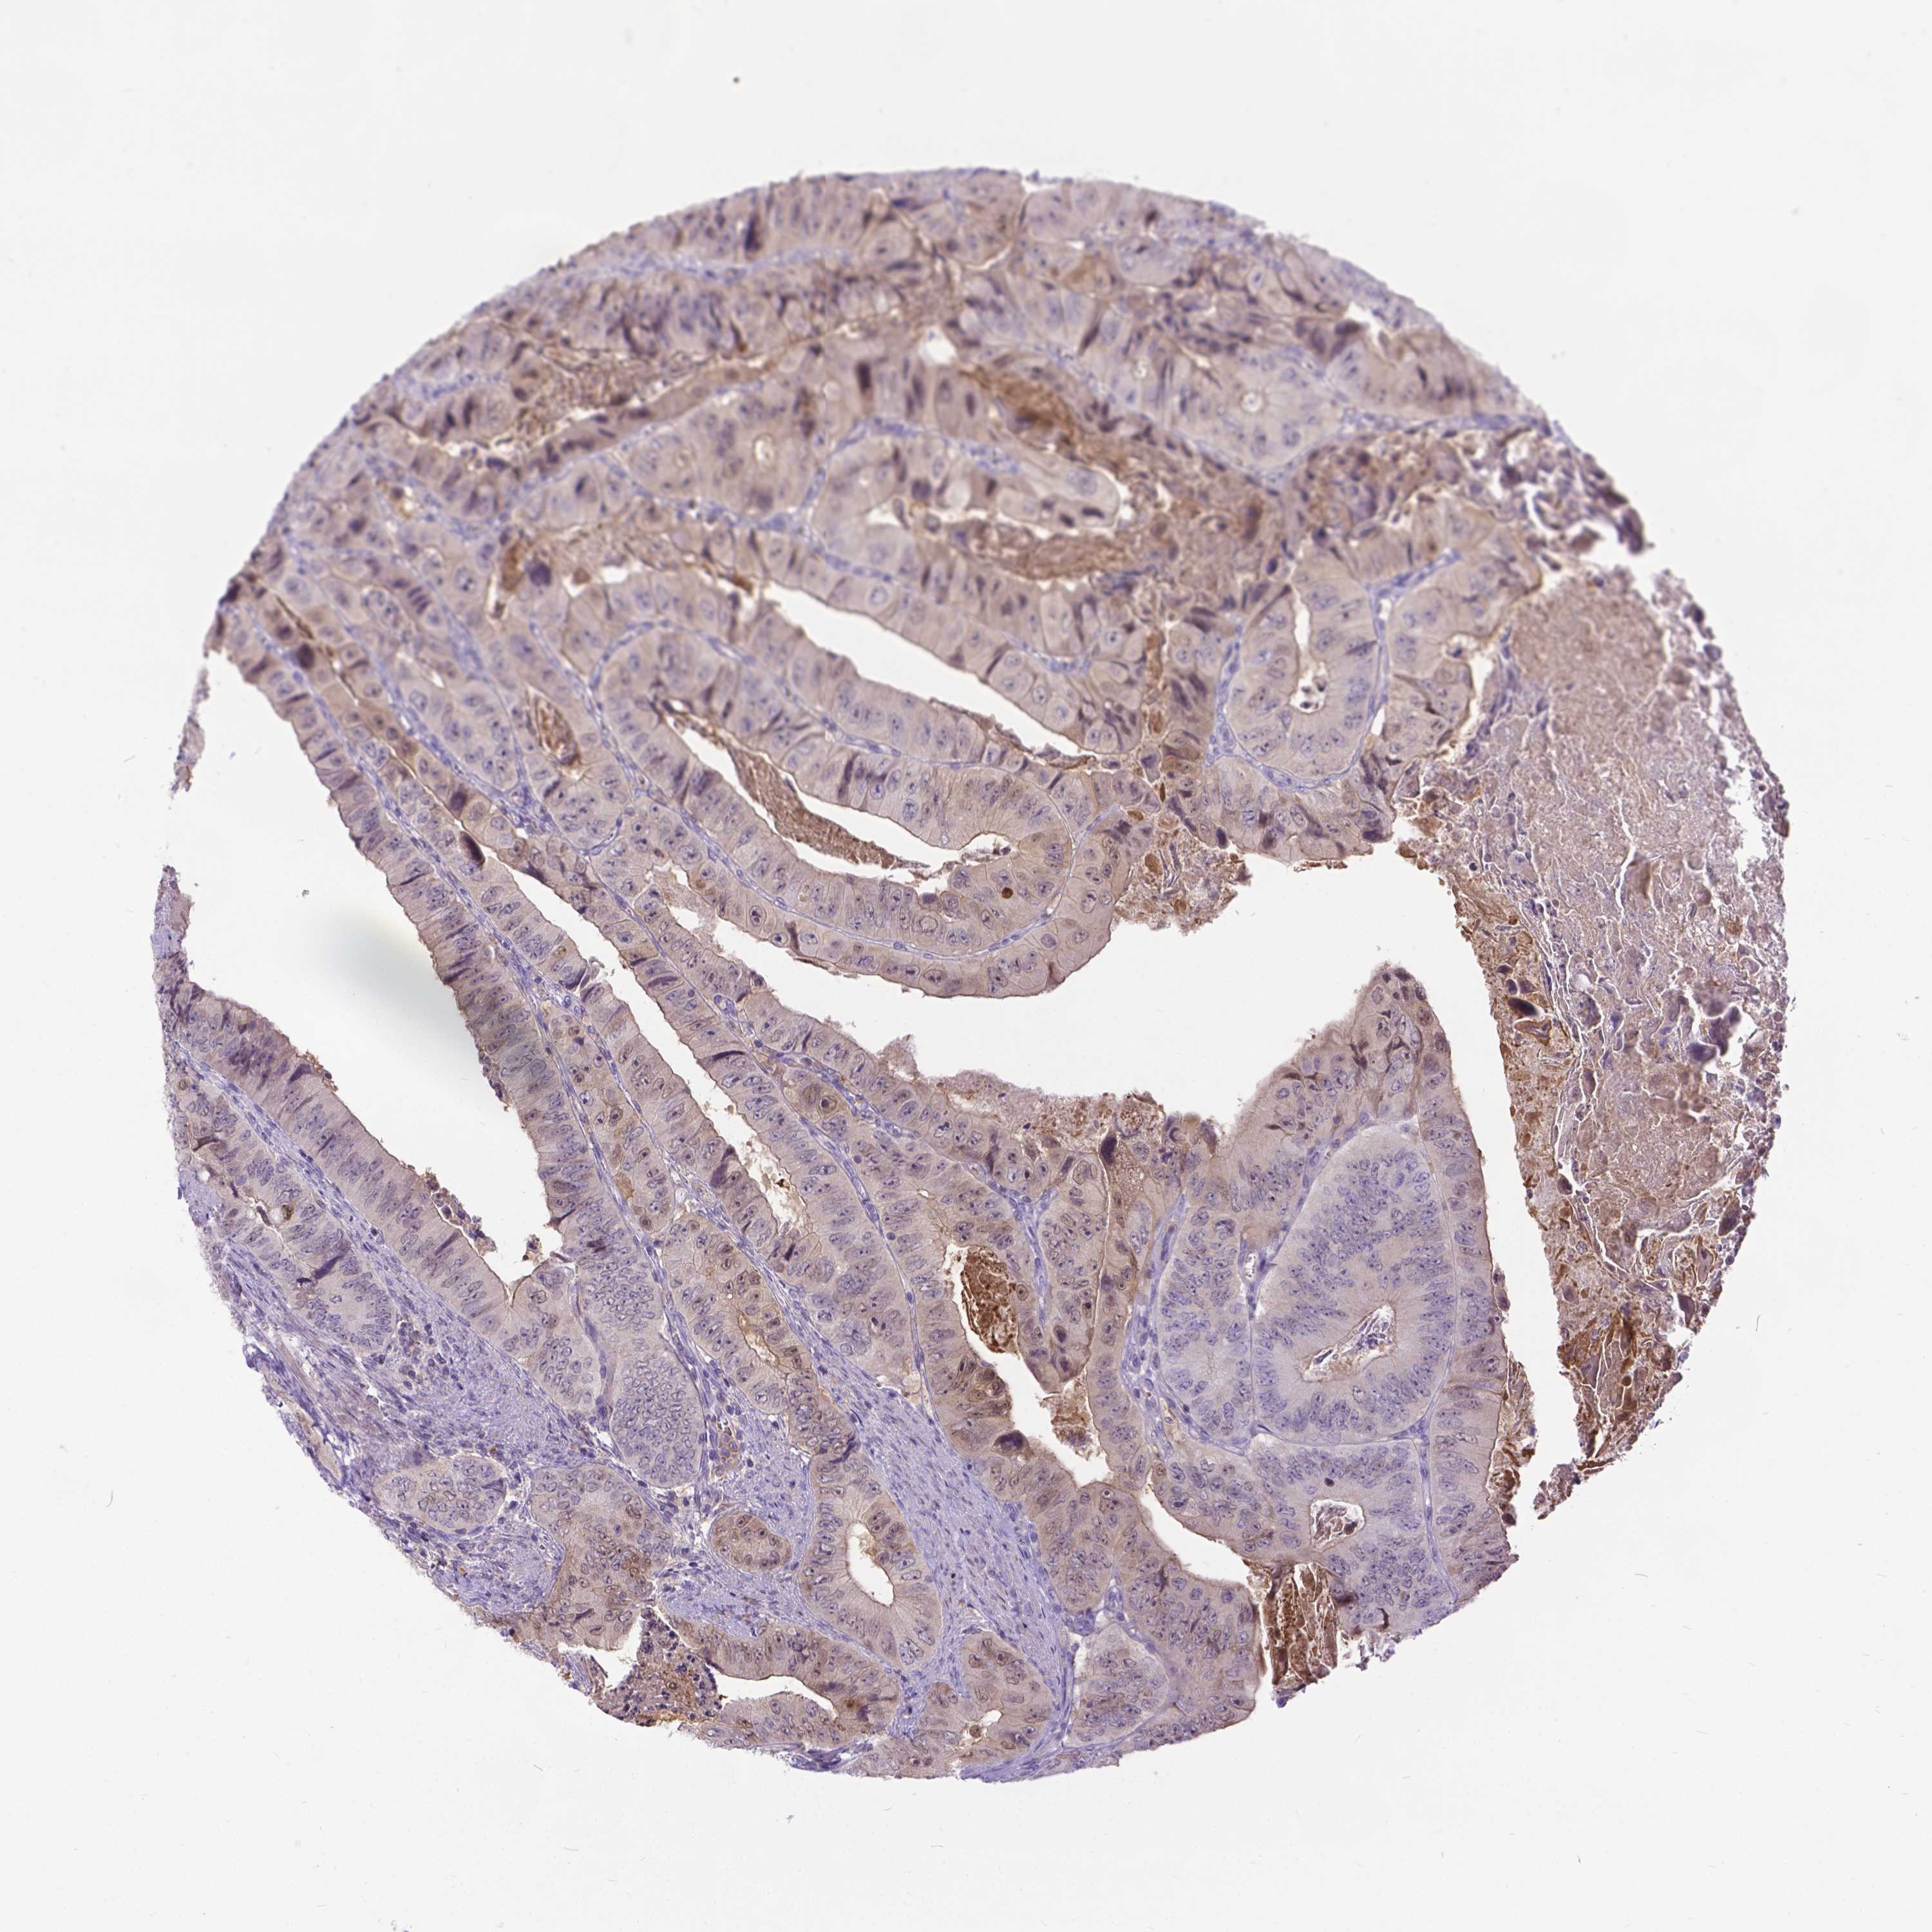

CANCER COLORECTAL CANCER Show tissue menu

Colorectal cancer

Colon adenocarcinoma